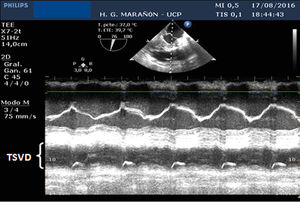

En el ecocardiograma transesofágico (ETE) realizado a continuación se objetivó buena función biventricular con disminución de la contractilidad del tracto de salida del ventrículo derecho (TSVD) como única alteración (fig. 2).